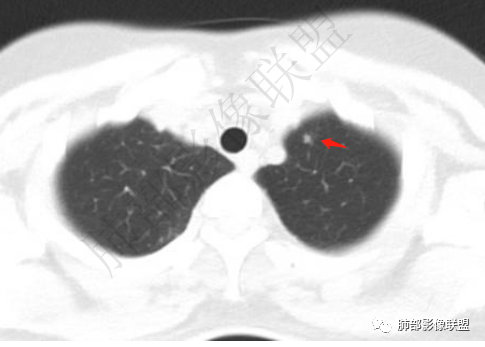

青年女性,胸痛1年,慢性病程

胸膜多个结节,附近胸壁脂肪间隙密度增高,提示有胸壁蔓延或侵犯。

1.胸膜多发结节,边缘比较光滑,累及胸壁(胸痛也符合,一年),表现为脂肪间隙密度增高,最大的病灶累及肺内,附近有渗出,但是无放射状表现,增强中央有坏死灶,一月后似有缩小,肋骨完整未见破坏,支持炎性可能大!